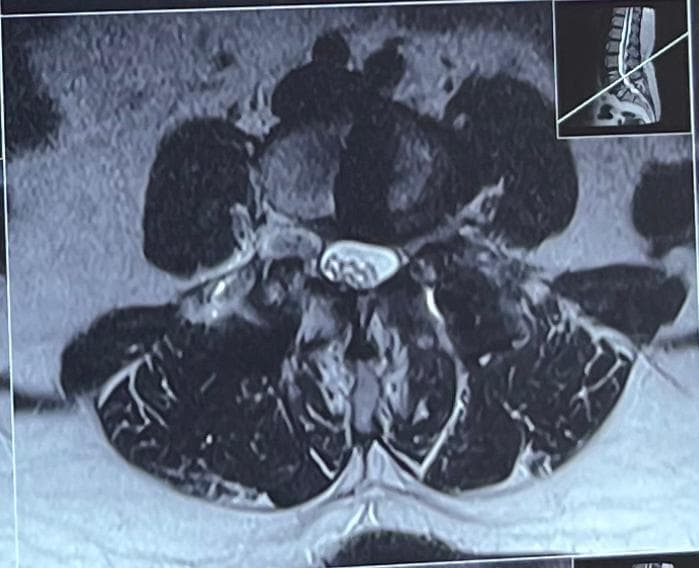

- Spinal canal stenosis is condition of spine where spinal canal become narrow. This put pressure over the spinal cord and nerves passing through it.

The diagnosis depends on complaints and a physical examination. Following are some examples: